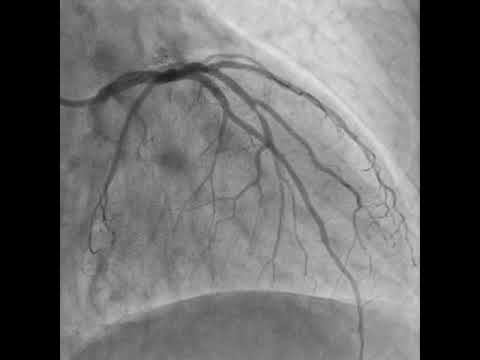

PCI to LCX-OM bifurcation using DK crush technique (case 5)(Delta Cath.Lab-Zagazig)

CRUSH TECHNIQUE STENTING OF LAD - D1 BIFURCATION

Trifurcated left main with poor ejection-fraction treated with DK-Crush technique